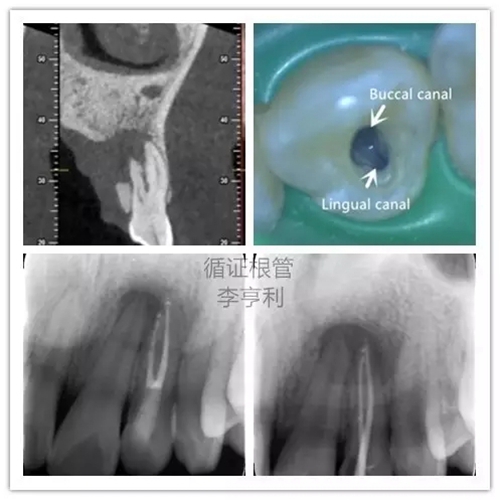

5,根管解剖的評估

上頜側(cè)切牙擁有雙根管

在CBCT的掃描中,根管形態(tài)能在三維的條件下評估,能準(zhǔn)確顯示根管數(shù)量和多個(gè)根管之間的聯(lián)系。根據(jù)Matherne et al. (2008)的間接體外研究(ex vivo),牙體牙髓??漆t(yī)生單憑閱讀數(shù)碼X片,即使一個(gè)牙齒進(jìn)行多個(gè)角度拍攝,還是有40%的樣本牙齒出現(xiàn)至少一個(gè)遺漏根管。

對于最容易被疏忽的上頜磨牙MB2根管,CBCT正確判斷其是否存在的幾率高達(dá)79%,與金標(biāo)準(zhǔn)的牙齒切片(sectioning)準(zhǔn)確率無統(tǒng)計(jì)學(xué)上的區(qū)別(Blattner et al. 2010)。所以,即使對于非手術(shù)性的根管再治療(non-surgical retreatment),CBCT也能提供巨大的治療價(jià)值。